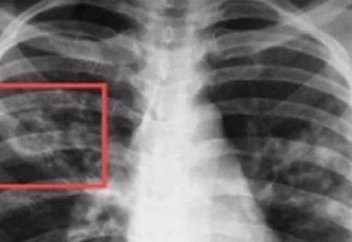

Туберкулезге шалдықпас үшін нені ескеру қажет?